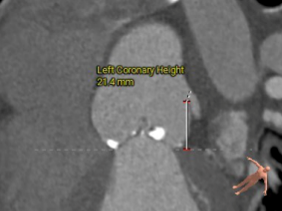

左冠开口高度:21.4mm

右冠开口高度:16.3mm

左窦瓣叶长度:20.8mm

右窦瓣叶长度:19.1mm